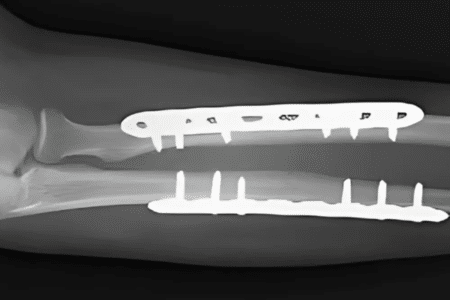

1. Fracture fixation

- Procedure: Surgeons realign broken bones and stabilize them using pins, screws, or metal plates.

- Ideal for: Complex or displaced fractures that cannot heal properly with a cast or splint.

- Benefits: Ensures correct alignment, faster recovery, and reduced chances of long-term deformity or weakness.